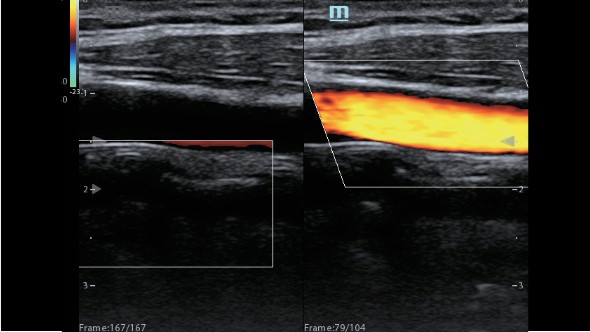

Клинические изображения